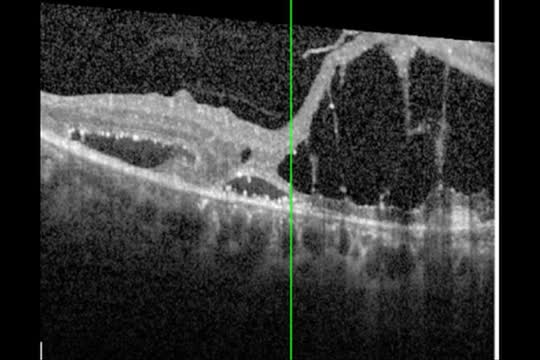

Retained PFO After Autologous Retinal Transplant: A Cause for Concern?

Carl Regillo, MD; Maria Berrocal, MD; Prof. David Keegan; and Tamer Mahmoud, MD, PhD

Patient Management After Autologous Retinal Transplant